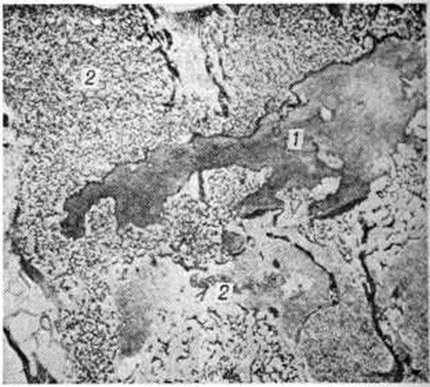

Рис. 4.

Гистотопограмма позвонка при болезни Педжета: межпозвоночный диск (1) истончён, его поверхностные отделы неровные, ткань диска частично замещена однородной, функционально недифференцированной губчатой костной тканью; 2— тела позвонков; × 2.

В позвоночнике изменения локализуются в теле и дуге одного или нескольких, смежных или близко расположенных позвонков. В процесс вовлекаются крестцовые, грудные или поясничные, реже шейные позвонки. Весь позвоночный столб никогда не поражается. Изменённые позвонки увеличиваются, передняя и боковые поверхности их сглаживаются. Нередко они сплющиваются, выдвигаясь за пределы нормальных границ позвоночного столба, деформируя позвоночный канал и межпозвоночные отверстия. На распилах (рисунок 3) структура позвонков неоднородная, участки разрежения чередуются с груботрабекулярными тяжами, более компактны их периферические отделы (рентгенологически — трабекуляризация, рисунок «рамы»). Местами костная ткань принимает вид мелкозернистой пемзы. Патологически изменённая костная ткань может замещать межпозвоночные диски, поверхность которых становится как бы изъеденной (рисунок 4). Возможно преобразование смежных сегментов в однородную функционально недифференцированную костную ткань. Опорная функция позвоночника снижается, возникают осложнения, обусловленные сдавлением спинного мозга и спинномозговых нервов.